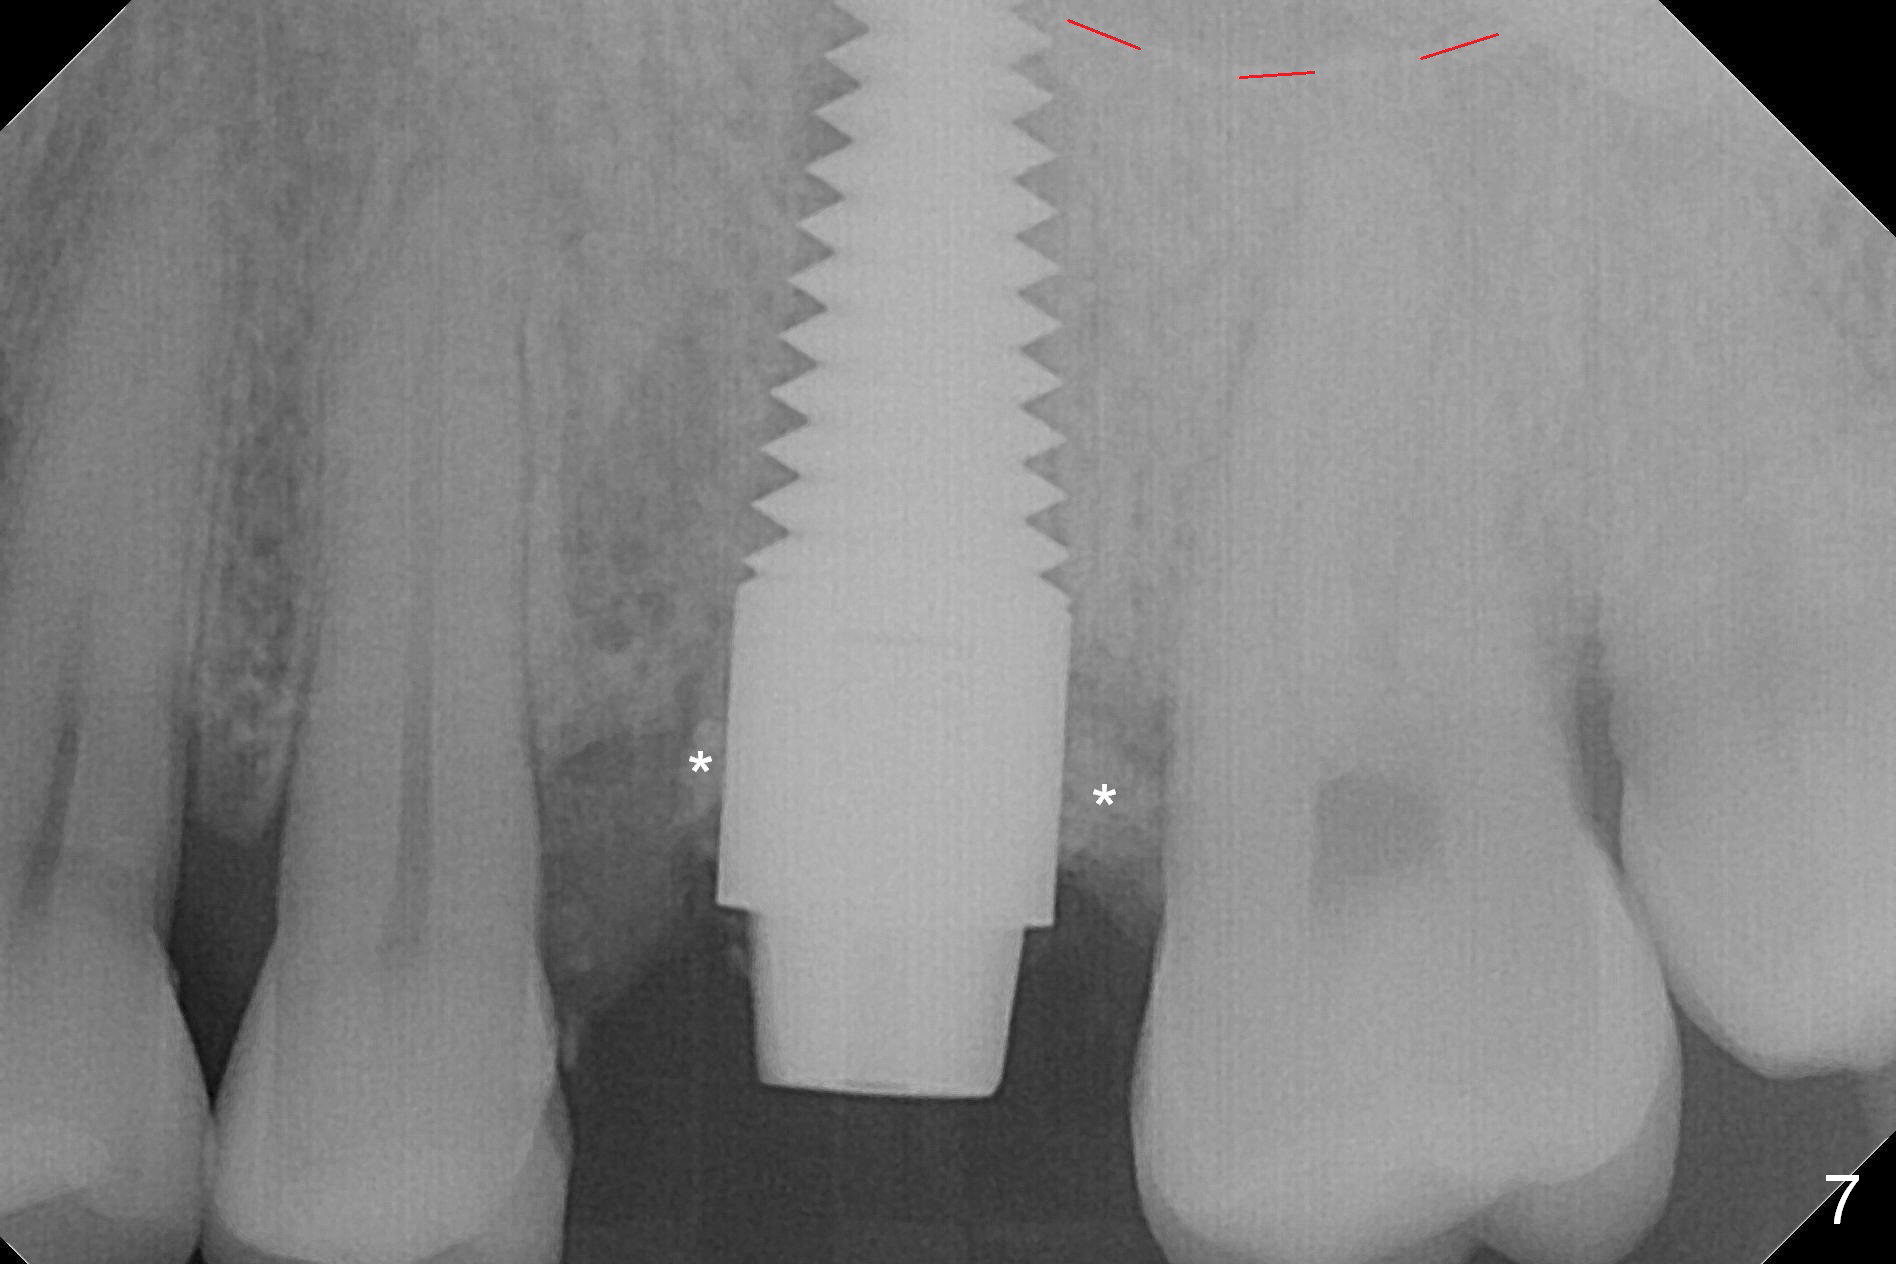

The septum perforates into the distobuccal socket when 4.3 mm drill is being used. The sinus floor bone (Fig.5 *, Fig.6-8 red dashed line) has to be used for primary stability. Finally a 6x20 mm tap achieves stability apparently by engaging to the mesial and distal walls of the socket (Fig.6). The insertion torque of a 6x20 mm tissue-level implant is > 60 Ncm (Fig.7) with allograft packed into the remaining socket (*).